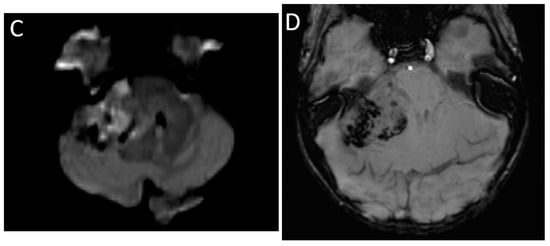

| Pineoblastoma | Pineal region | Heterogenous, ‘explode’ pineal calcification Diffusion restricting Enhancement variable |

| Germ cell tumor | Pineal and/or suprasellar region | Heterogenous, usually calcified, ‘engulf’ pineal calcification Diffusion restricting Enhancement usually present |